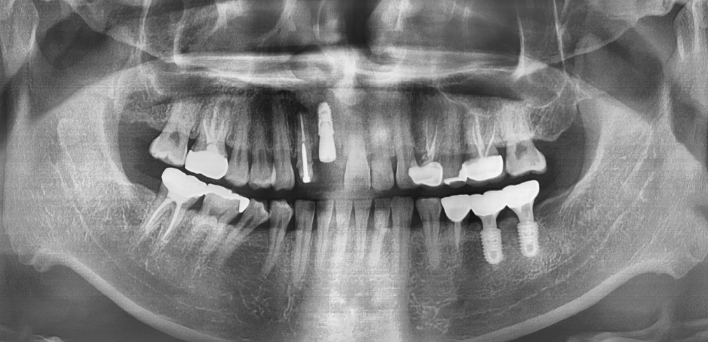

임플란트 Before & After

The seoul dental clinic

※ 더서울치과의원은 의료법을 준수하며 위 케이스는 실제 환자의 동의를 얻은 사례로 치료 전, 후가 동일한 환경에서 촬영되었습니다.

환자 케이스에 따라 부작용이 발생할 수 있습니다. 이 부분은 의료진의 충분한 상담과 체크를 통해 예방하고 줄일 수 있습니다.

[임플란트 부작용] 수술 후 관리가 소홀할 경우 출혈, 주위염 등의 부작용이 발생할 수 있어 구강 위생을 철저히 유지하고, 정기적인 검진을 통해 상태를 점검하는 것이 중요합니다.